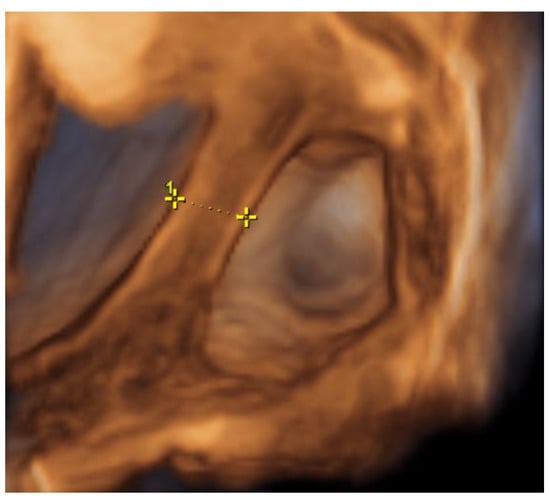

On the 22nd week of gestation, the woman was admitted to tertial level hospital complaining of pain in hypogastric and left iliac regions of the abdomen, provoked by physical exercise. Ultrasonography was performed, the remaining unchanged mass in the left cornu of the uterus was observed as well as an intraamniotic septum in the lower segment of the uterus, as shown in Figure 5 and Figure 6. The fetal growth of the intrauterine pregnancy was unaffected and matched its gestational age. Conservative treatment was chosen, the pain resolved and the patient was discharged in 2 days.

Figure 6. Left cornu of the uterus visualized by 3D transabdominal ultrasonography at the 22nd week of gestation.